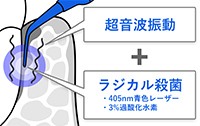

ブルーラジカルとは、歯周病の原因となる細菌を、薬剤と光の力を組み合わせて除菌する新しい歯周病治療です。歯ぐきの中に過酸化水素を入れ、専用の青色レーザーを照射することで、強い殺菌作用を持つ成分(ラジカル)を発生させ、歯周ポケットの奥に潜む細菌を99.99%殺菌する世界初の非外科的歯周病治療器です。

ブルーラジカルは、3%過酸化水素と405nmの青色レーザーを組み合わせ、歯周ポケット内の細菌に着目した治療法です。スケーリングによる清掃とあわせて行うことで、歯周病治療の選択肢の一つとして用いられます。